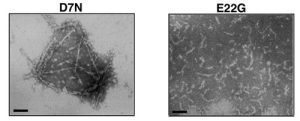

脳内に分泌されたAβが凝集する過程で神経細胞死を引き起こすことは、アルツハイマー病発症に重要なステップであると考えられている。そして近年、神経細胞死を起こすAβの分子種としてprotofibrilと呼ばれる可溶な凝集中間体が注目されている。今回堀らはAβ内部に位置し、家族性アルツハイマー病を引き起こす鳥取型(D7N)、英国型(H6R)の二つの点突然変異に注目し、これらの変異が構造変化の核形成には影響を与えないものの、その後の線維伸長を促進することを明らかにした。さらに線維伸長過程を詳細に検討したところ、二つの変異はArctic型変異(E22G)で見られるようなprotofibril形成の促進(図右)とは異なり、アミロイド線維自身の形成を促進している(図左)ことを見いだした。この結果は、protofibrilだけでなくアミロイド線維形成の促進もアルツハイマー病発症を引き起こすことを意味し、今後Aβ凝集メカニズム解明、そして凝集抑制を指標とするアルツハイマー病根本治療薬の開発に重要な知見を与えるものである。